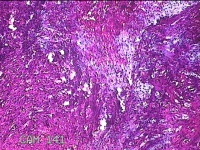

右卵巢囊肿壁

性别

女

年龄

36岁

临床诊断

右卵巢子宫内膜异位囊肿 盆腔炎性疾病后遗症

一般病史

痛经5年,加重3月。

标本名称

大体所见

灰白暗红色囊壁样组织4.5x3.3x0.8cm一堆,表面光滑,因已切开,囊内容物已流失,囊壁厚0.1cm。

图2